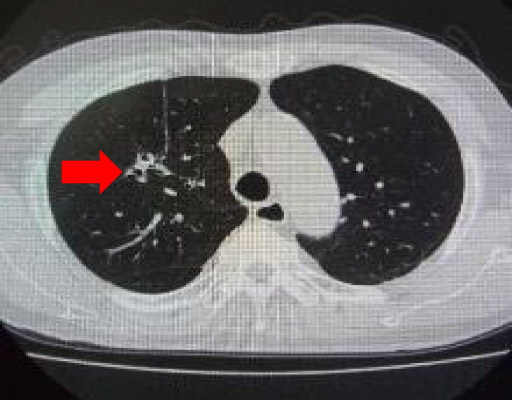

肺CT画像

CTの検出感度は93.3~94.4%と高く早期の肺がんを検出する形態的診断法として現時点で最も有力な手段になります。(胸部X写真の検出感度は59.6~73.5%)参考文献: